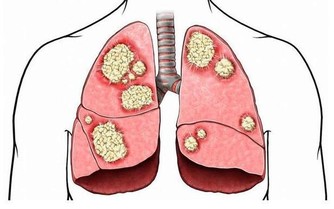

- 降低慢性疾病風險:選擇富含膳食纖維的食物可改善心血管健康,降低高血壓、糖尿病的風險。

- 身體素質提升:改善免疫系統功能,減少罹患慢性病的風險。